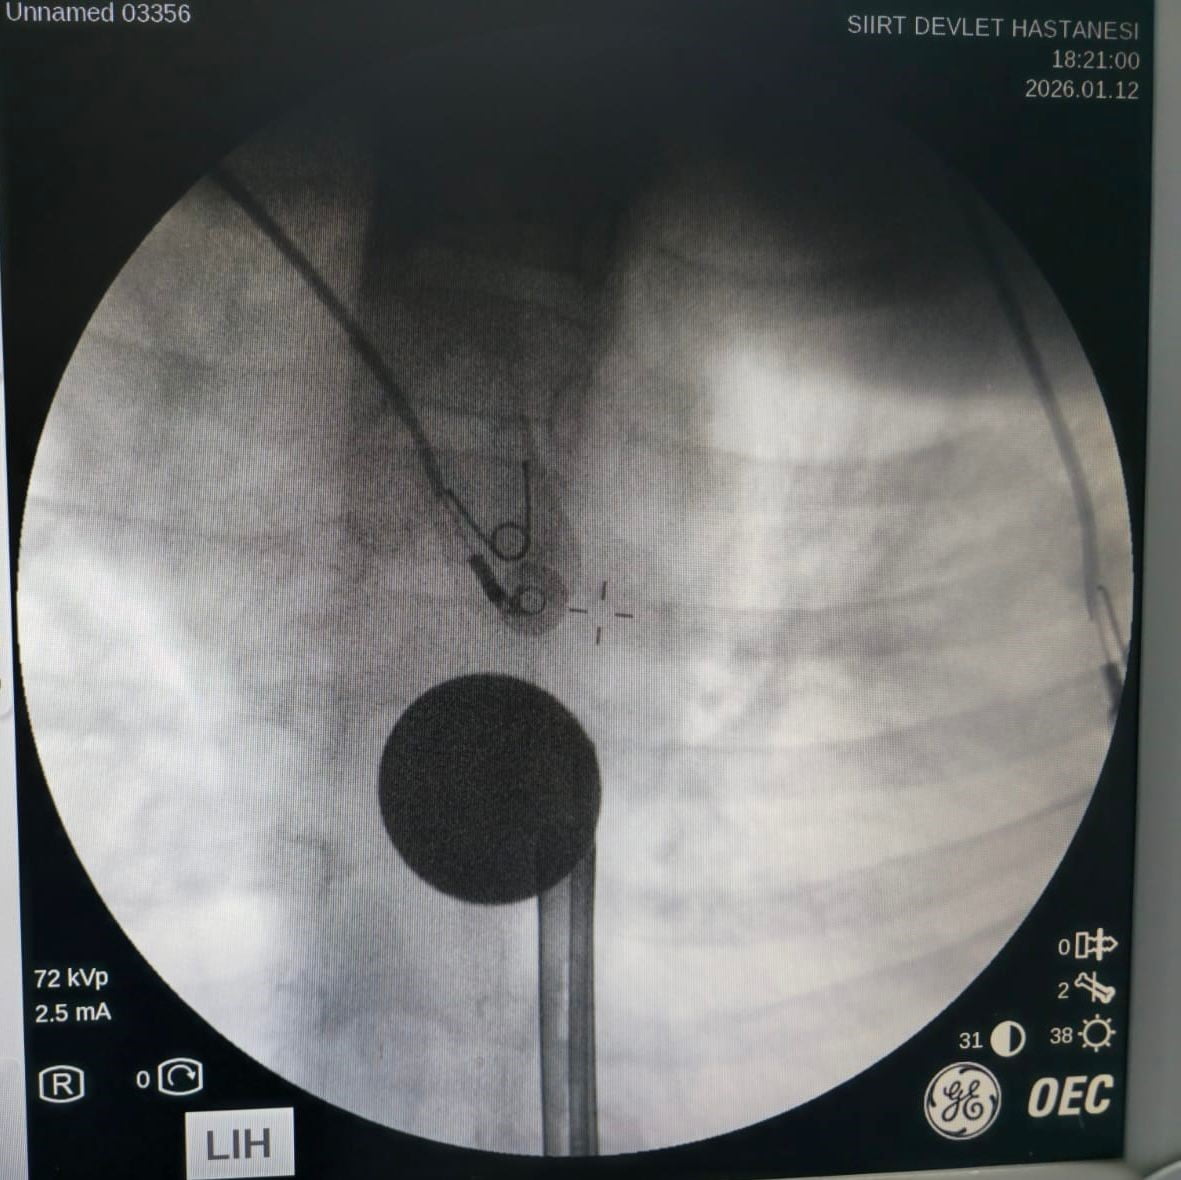

Yabancı cisim yutma şikayetiyle ailesi tarafından Siirt Eğitim ve Araştırma Hastanesine getirilen 8 yaşındaki Y.K., yapılan ilk değerlendirme ve görüntüleme tetkiklerinin ardından ilgili branşlarca operasyona alındı.

Y.K.'nın yemek borusuna kadar ilerlediği tespit edilen madeni 5 lira, gastroenteroloji uzmanı Dr. Yaren Dirik ve kulak burun boğaz hekimi Yasin Gökçınar tarafından yapılan müdahale ile çıkartıldı.

Vakada gastroenteroloji ile KBB ekiplerinin koordineli müdahalesi ve yapılan görüntülemenin, komplikasyon riskinin azaltılmasında belirleyici olduğu bildirildi.